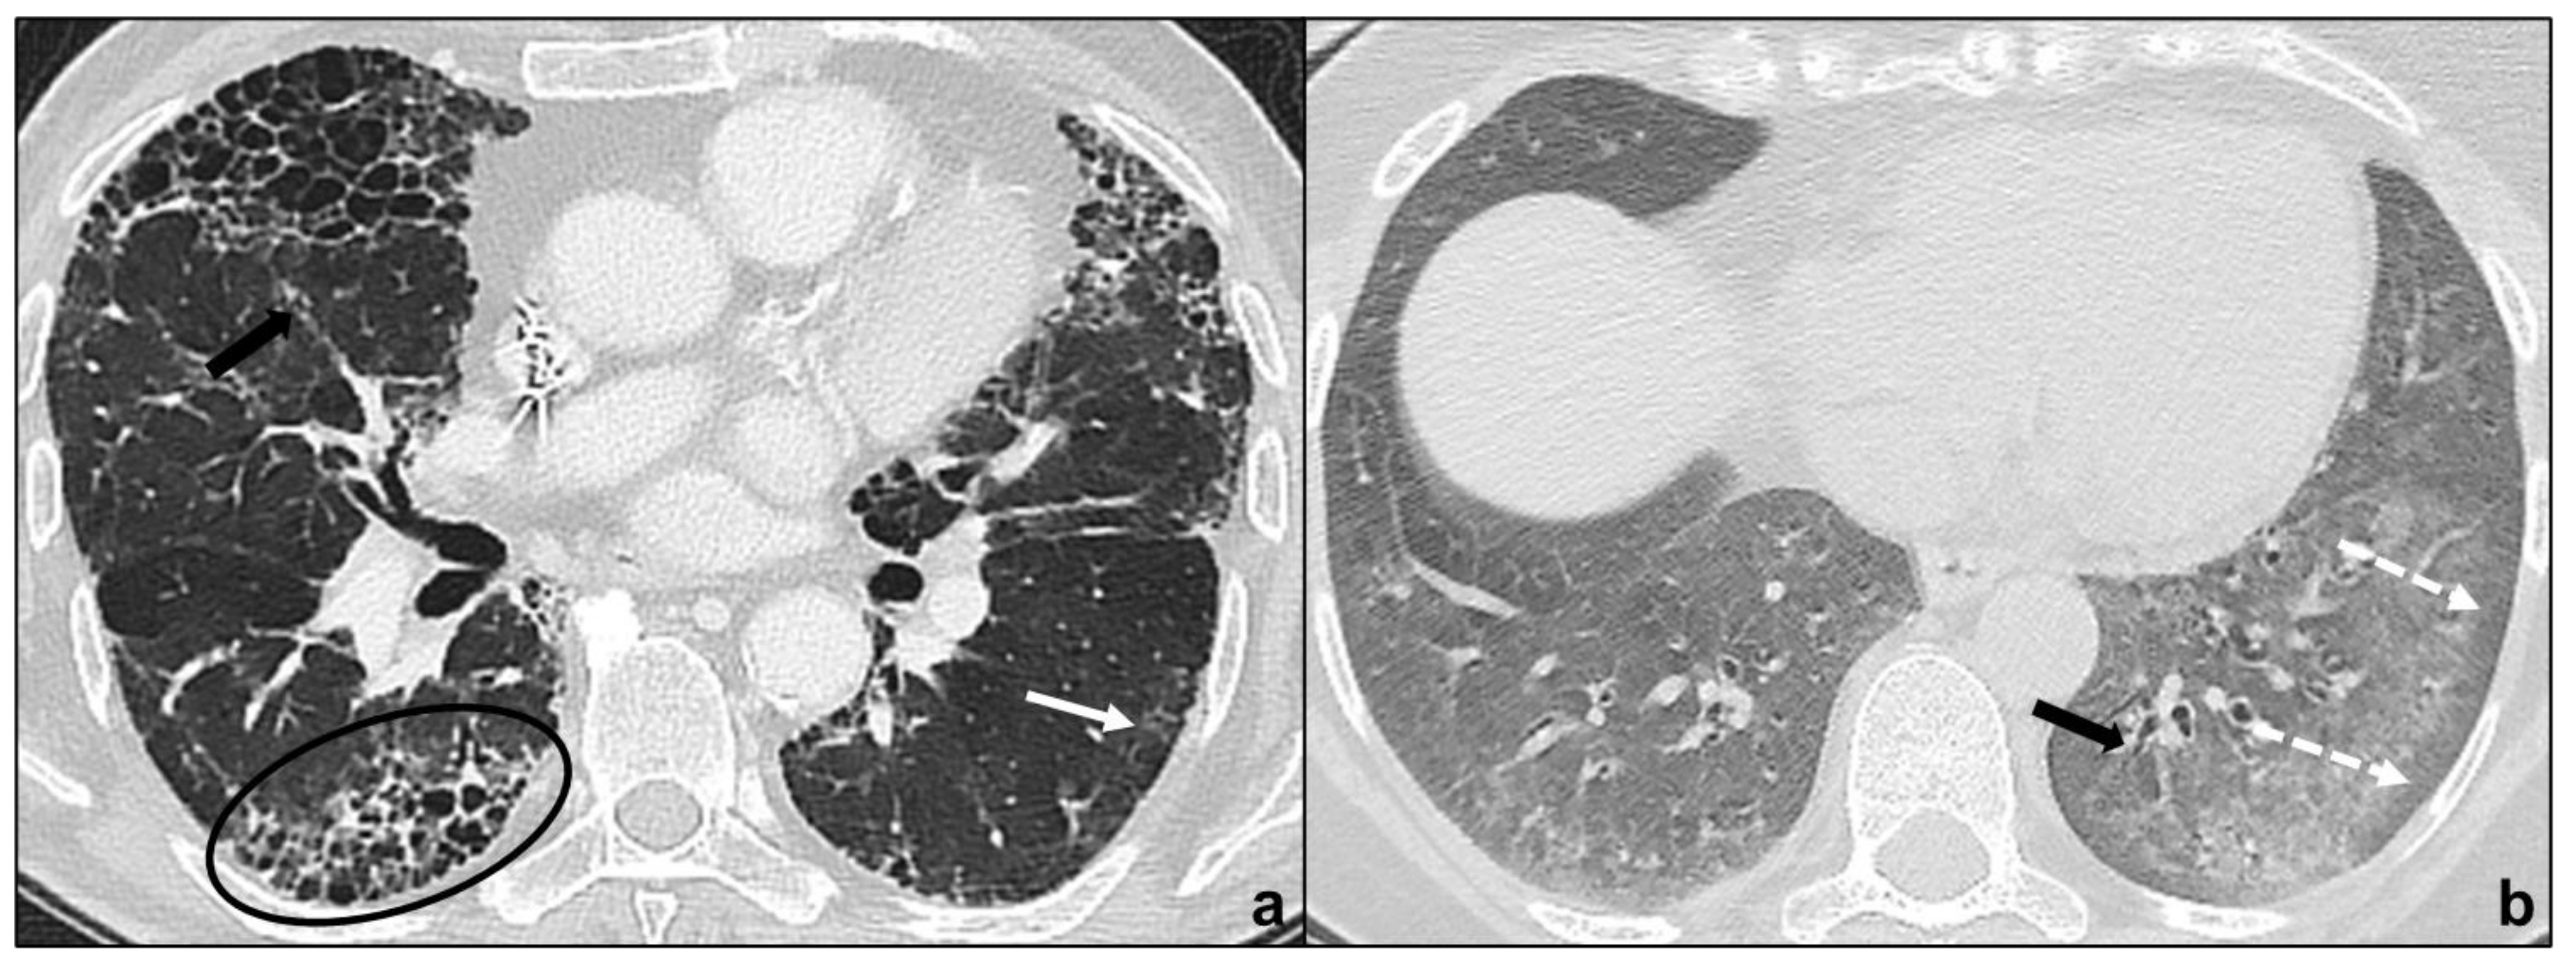

Figure 3.

Major IIPs: Chronic Fibrosing IIPs. In (a), the UIP pattern is characterized by traction bronchiectases (black arrow in (a)), irregular reticular opacities, basal and subpleural macrocystic honeycombing (black oval in (a)), and non-prevalent ground-glass opacities (back arrow in (a)); in (b), the NSIP pattern is characterized by the bilateral, basal and diffuse ground glass with typical subpleural parenchymal preservation (white dotted arrows in (b)), coexisting with irregular reticular opacities and traction bronchiectasis (black arrow in (b)).

UIP is characterized by macrocystic honeycombing as a specific marker, architectural distortion with traction bronchiectases, irregular, reticular opacities, and decreased lung volumes [31]. Apicobasal gradient, heterogeneous involvement, and subpleural distribution are typical features [18]. Ground glass opacities are present, especially during disease exacerbation, but these opacities are limited in extent [19], and often accompanied by superimposed reticular patterns. There is a clear demarcation between healthy pulmonary parenchyma and UIP affected pulmonary parenchyma [5,32]. Occasionally, millimetric nodular calcifications may be appreciated [33]. Mediastinal lymphadenopathies [34] and coexisting emphysema may occur. Patients presenting with typical UIP features do not undergo lung biopsy and are diagnosed as IPF patients [18] (Figure 3a).

Probable UIP does not show radiological honeycombing, but the coexistence of peripheral traction bronchiectasis, subpleural and basal reticular abnormalities, and non-predominant ground-glass opacities; indeterminate for UIP is assigned to HRTCs demonstrating features of fibrosis without UIP/probable UIP criteria; alternative diagnosis is assigned to patterns suggesting a fibrotic lung disease different from IPF. In all previous cases, lung biopsy is required [18].

HRCT shows peripheral, basal, and symmetric ground glass opacities in the majority of patients, and irregular, reticular opacities and traction bronchiectases are extremely common findings [5,35,36]. The preservation of subpleural pulmonary tissue and the absence or sparse presence of microcystic honeycombing are typical and helpful in distinguishing NSIP from UIP [37]. Other key features to exclude UIP are the absence of an apicobasal gradient, finer reticular pattern and micronodules [19]. Consolidations are uncommon and suggest the co-presence of OP [5]. These radiological features suggest that a variable degree of fibrosis is appreciable in the majority of NSIP patients and justifies the inclusion in the chronic fibrosing IIPs [10] (Figure 3b).